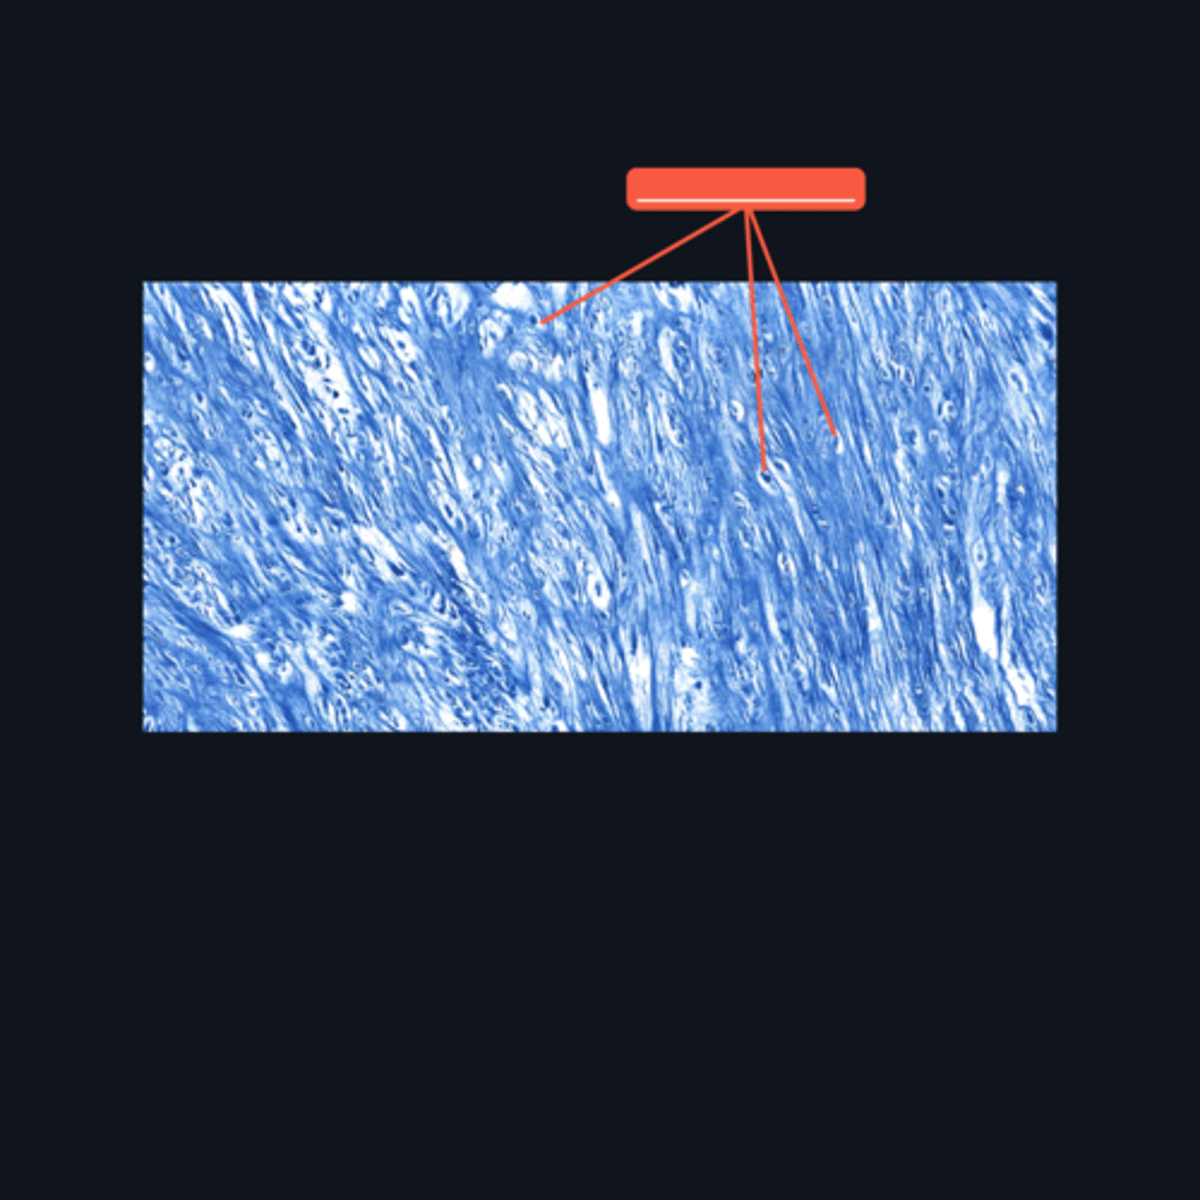

Fibrocartilage; intervertebral disc, articular disc, glenoid and acetabular labra

What type of cartilage is in the image? Where is this specific type of cartilage found?

Collagen fibers

This type of cartilage is abundant in what fibers?

Dense regular connective tissue; chondrocytes; lacunae

This cartilage is commonly mistaken as _____. However, when examined closely, _____are contained in _____ (identify pointed structures), making it a cartilage.